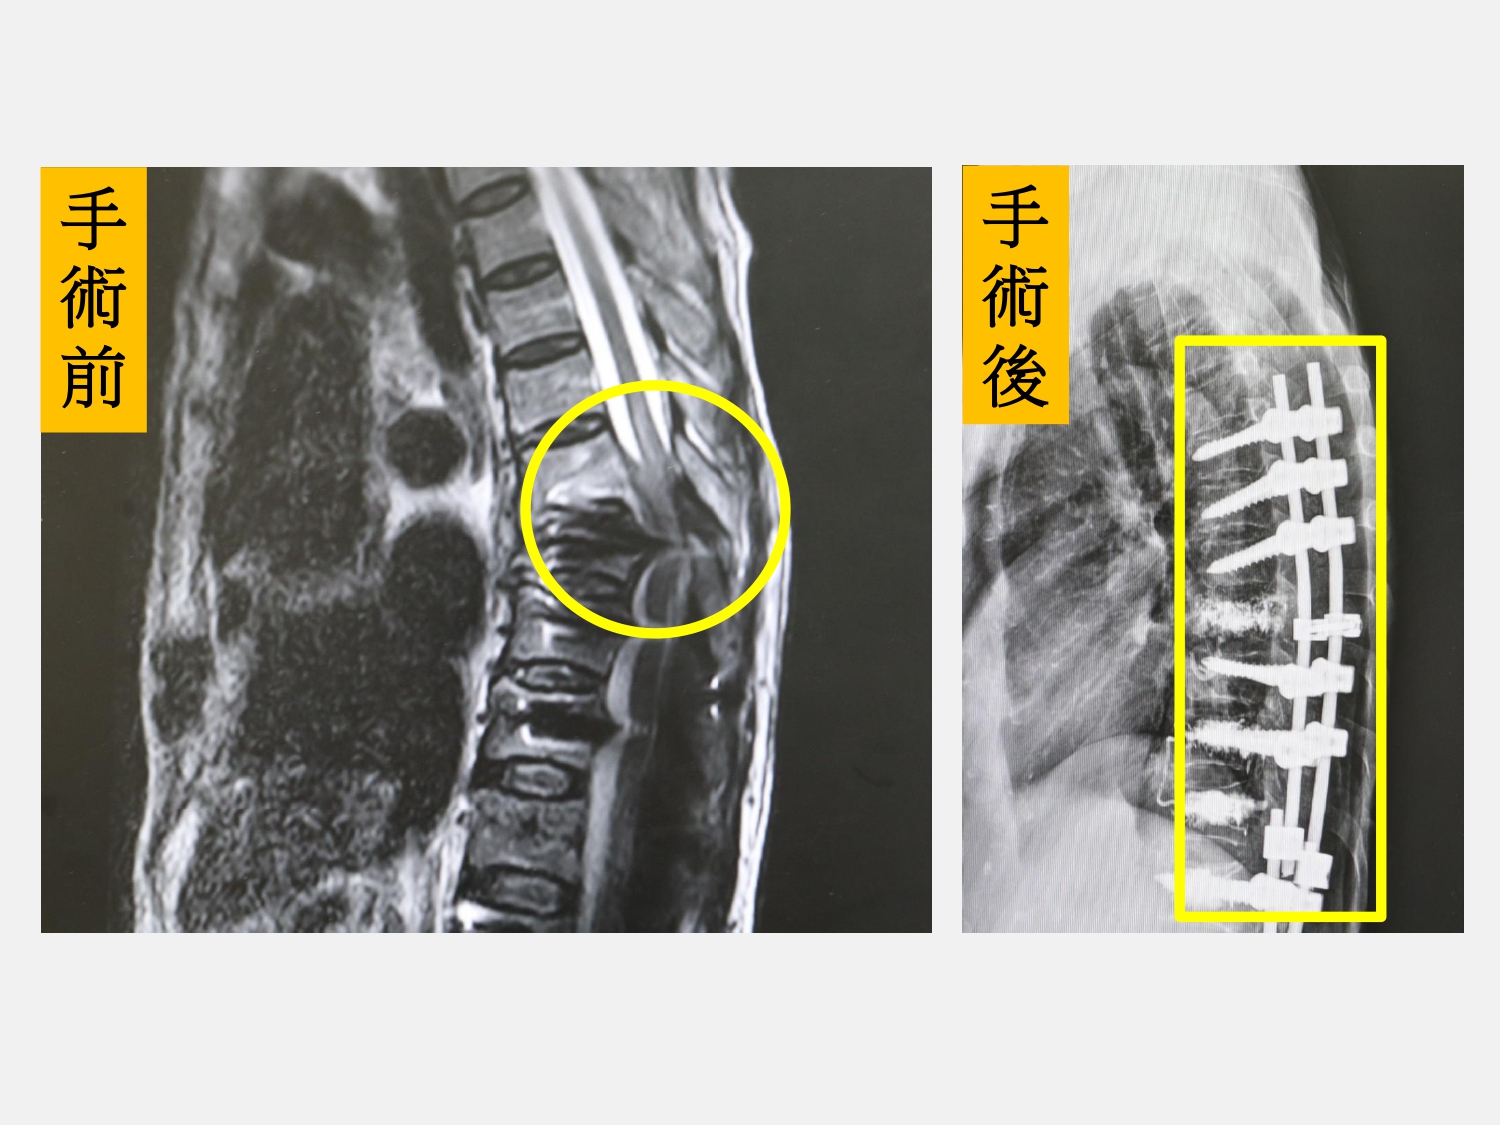

急診檢查發現,患者雙側大腿與小腿幾乎無力,僅剩腳踝可輕微活動,核磁共振檢查顯示,第七胸椎發生爆裂性骨折並壓迫脊髓,醫療團隊立即進行緊急手術。術後隔天,患者大腿已出現些微活動反應,後續除接受骨質疏鬆症藥物治療外,待疼痛緩解後也由復健科安排積極復健訓練,約一個月後已能使用四腳助行器緩慢行走,生活功能逐步改善。

陳盈佑指出,這名77歲婦人先前的固定範圍自第八胸椎延伸至整個腰椎,此次骨折則發生在第七胸椎,手術除進行脊椎板切除減壓外,也同步延長脊椎固定並完成後融合。醫療團隊僅打開原本上段傷口進行接合延長,不需大範圍重新手術,可有效縮短手術時間,並降低麻醉與手術對高齡患者的身體負擔。陳盈佑強調,雖然長者及家屬常對手術風險有所顧慮,但若脊髓已受壓並出現癱瘓,仍須及早手術介入,否則恐長期臥床,影響後續生活品質。